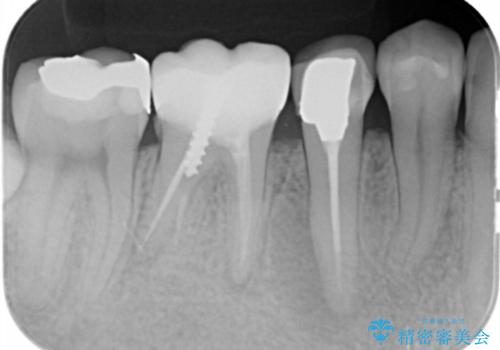

深い虫歯 セラミッククラウンの精度を高める歯周外科手術

- 歯ぐきからの排膿や出血、根尖病変の存在により他院で抜歯を提案され、歯を残す方はないかと当院に相談に見えました。

マイクロスコープを用いた根管治療を行ったのち、深い虫歯に起因する歯ぐきの腫れ・出血を改善すべく歯周外科を行いました。